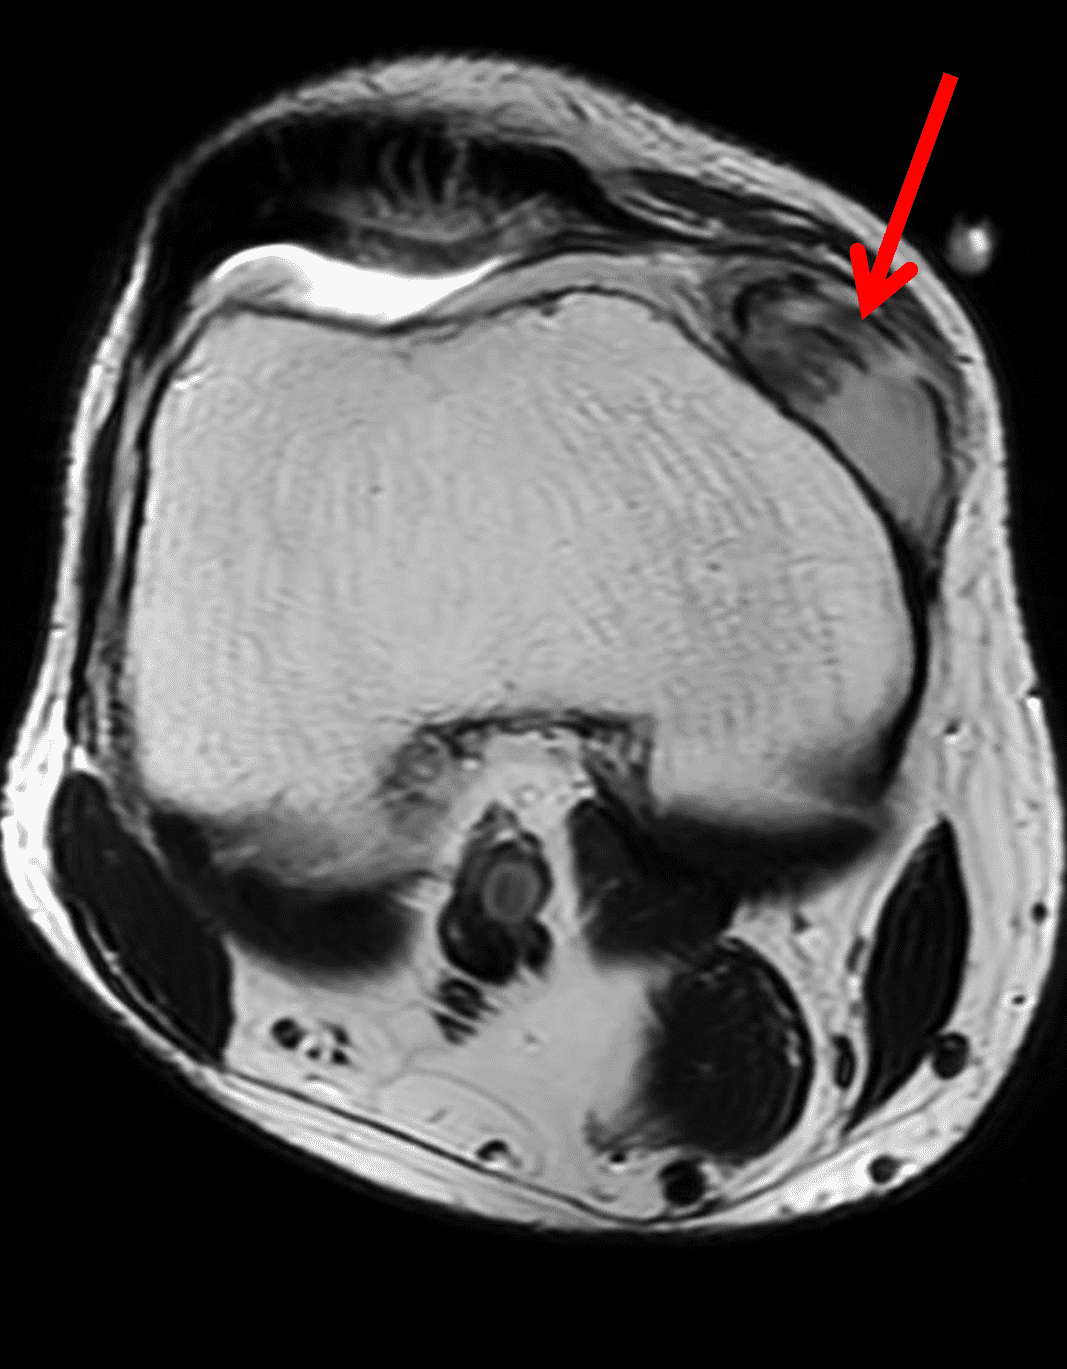

Figure 2: An ill-defined, infiltrative mass superficial to and involving most of the distal quadriceps tendon (red arrows) has intermediate signal on the fat-suppressed fluid-sensitive (2A) and proton density-weighted (2B) images, with faint marrow edema in the adjacent patella (yellow arrow).

Imaging characteristics are variable in different stages. On radiographs, in early stages, soft tissue swelling may be the only finding. With chronic gout, intra-articular or juxta-articular erosions with overhanging edges, and soft tissue mass with or without calcification can be seen, with relative preservation of joint spaces until late stage of disease.2-4,16,17 On MRI (Figures 2 and 9), tophi usually appear as intermediate T1 signal masses with variable T2 signal depending on the amount of calcification present, and somewhat variable contrast enhancement. On CT, tophi are usually hyperattenuating with or without calcifications. Gout may also present on imaging as focal or multifocal disease within a joint.2-4,16,17